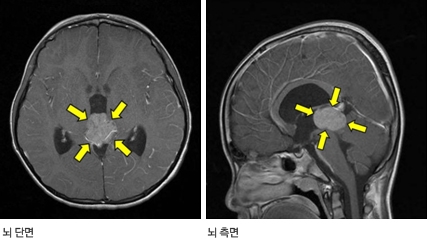

뇌 자기공명영상(MRI)이나 컴퓨터 단층촬영(CT)을 통해 송과체(멜라토닌이라는 호르몬을 분비하는 뇌 후부에 위치한 기관)나 뇌하수체 등에 종양의 유무를 확인한다. 자기공명영상(MRI)이나 컴퓨터 단층촬영(CT) 시 조영제를 투여하면 종양의 특징과 주변 부위로의 파급여부를 파악하는 데 큰 도움이 된다. 양전자 단층촬영(Positron emission tomography, PET)을 시행하여 같은 부위에 발생하는 다른 종양과 감별진단을 하기도 한다.

종양의 호발 부위인 송과체의 앞쪽은 뇌척수액이 흐르는 대뇌 수도관(cerebral aqueduct)이 위치하고 있어 종양에 의해 수도관이 눌릴 경우 수두증이 발생한다. 수두증으로 인해 두통, 구역, 구토, 보행장애 등이 나타난다.

종양이 중뇌의 시개(tectum, 덮개)를 압박하면 양쪽 안구를 위쪽으로 뜰 수 없으며(상향 주시 마비), 빛에 대한 동공반사에 이상이 발생한다. 주변 운동신경의 경로나 소뇌를 압박할 경우 보행장애, 미세운동의 장애, 마비 등의 증상이 발생할 수 있다.